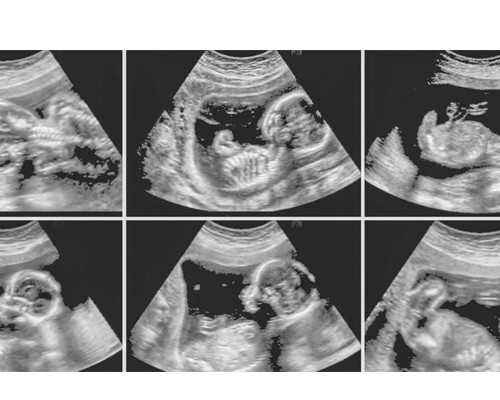

最近有一位来自甘肃张掖的姐妹说自己:18年检查出有子宫腺肌症,随后做了宫腹腔镜手术,然后医生说已经无自然受孕的可能,建议早点做试管婴儿,于是这里想问问子宫腺肌症做试管婴儿能有多大的成功率?